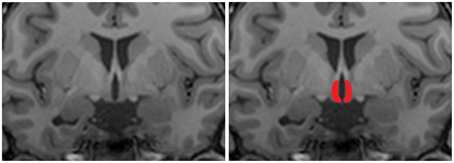

To analyze differences in hypothalamic and overall brain structure we performed manual segmentation of the hypothalamus to calculate hypothalamic volume and we performed VBM analysis to determine voxel-wise differences in volume between groups according to Holle et al. (2011). Manual segmentation of the hypothalamus was done based on morphological anatomical landmarks as described earlier (Goldstein et al., 2007; Klomp et al., 2012; Terlevic et al., 2013). A coronal view of an example segmentation of the hypothalamus is shown in Figure 2. Differences in hypothalamic volume between patients and controls were tested using an independent samples t-test.

Figure 2. Coronal T1 weighted image of the hypothalamus. For structural analysis of the hypothalamus a region of interest was manually drawn on T1 scans. The left panel shows an representative coronal view of a T1 scans, the right panel shows an example hand delineated region of interest overlaid over the original image.